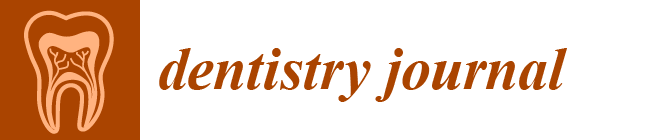

2.2.1. Model Preparation

2.2.2. Finite Element Model (FEM) Preprocessing